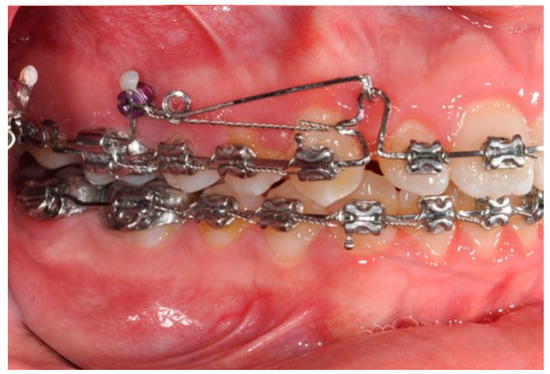

Figure 9. Canine and incisor distalization strategy: The cantilevers produce intrusion of the incisors and torque control during retraction.

In this case, right after the spontaneous eruption, a power chain from the right tad was used to derotate and distalize the right upper canine (Figure 8). On the upper arch, a 0.20 × 0.25 SS wire was prepared with modified “cactus-shaped” closing loops, with the aim to close the space between the canines and the laterals. The cactus loop has a double aim. First of all, it is used as a closing loop; activation is produced by tying the loop through a metallic ligature from the tads. Secondly, it serves as a hook for cantilevers. The cantilevers are made using 0.19 × 0.25 TMA. The retraction of the upper incisors is supported by two cantilevers applied distally on the tads. The cantilevers will support the mechanics in order to produce intrusion of the incisors and torque control during retraction [1] (Figure 9 and Figure 10).

The use of cantilevers on miniscrews is essential to maintain the class I molar relationship obtained after distalization. Indeed, a loss of molar anchorage not only affects the anterior positions of molars but also induces modifications to the overall vertical dimensions of the face [1]. While retracting the upper incisors using forces at the occlusal level, it is pivotal to control the moment produced by the force, which is responsible for the loss of incisor torque. The use of a cantilever produces a counteracting moment. This moment is also responsible for a certain amount of intrusion, which, in this case, was favorable. The distalization of molars can also be achieved through palatal anchorage [2]. Although this treatment strategy has proven to be efficient, the Biga system offers a valid alternative with a lower cost for the orthodontist and it represents a comprehensive treatment strategy for the dentition. Indeed, the main distalization techniques are presented as ends in themselves; however, in this article, an inclusive treatment strategy has been proposed that is not only aimed at producing distalization and controlling side effects. On the contrary, the Biga system is characterized by achieving several biomechanical advantages on both the upper and lower arches.